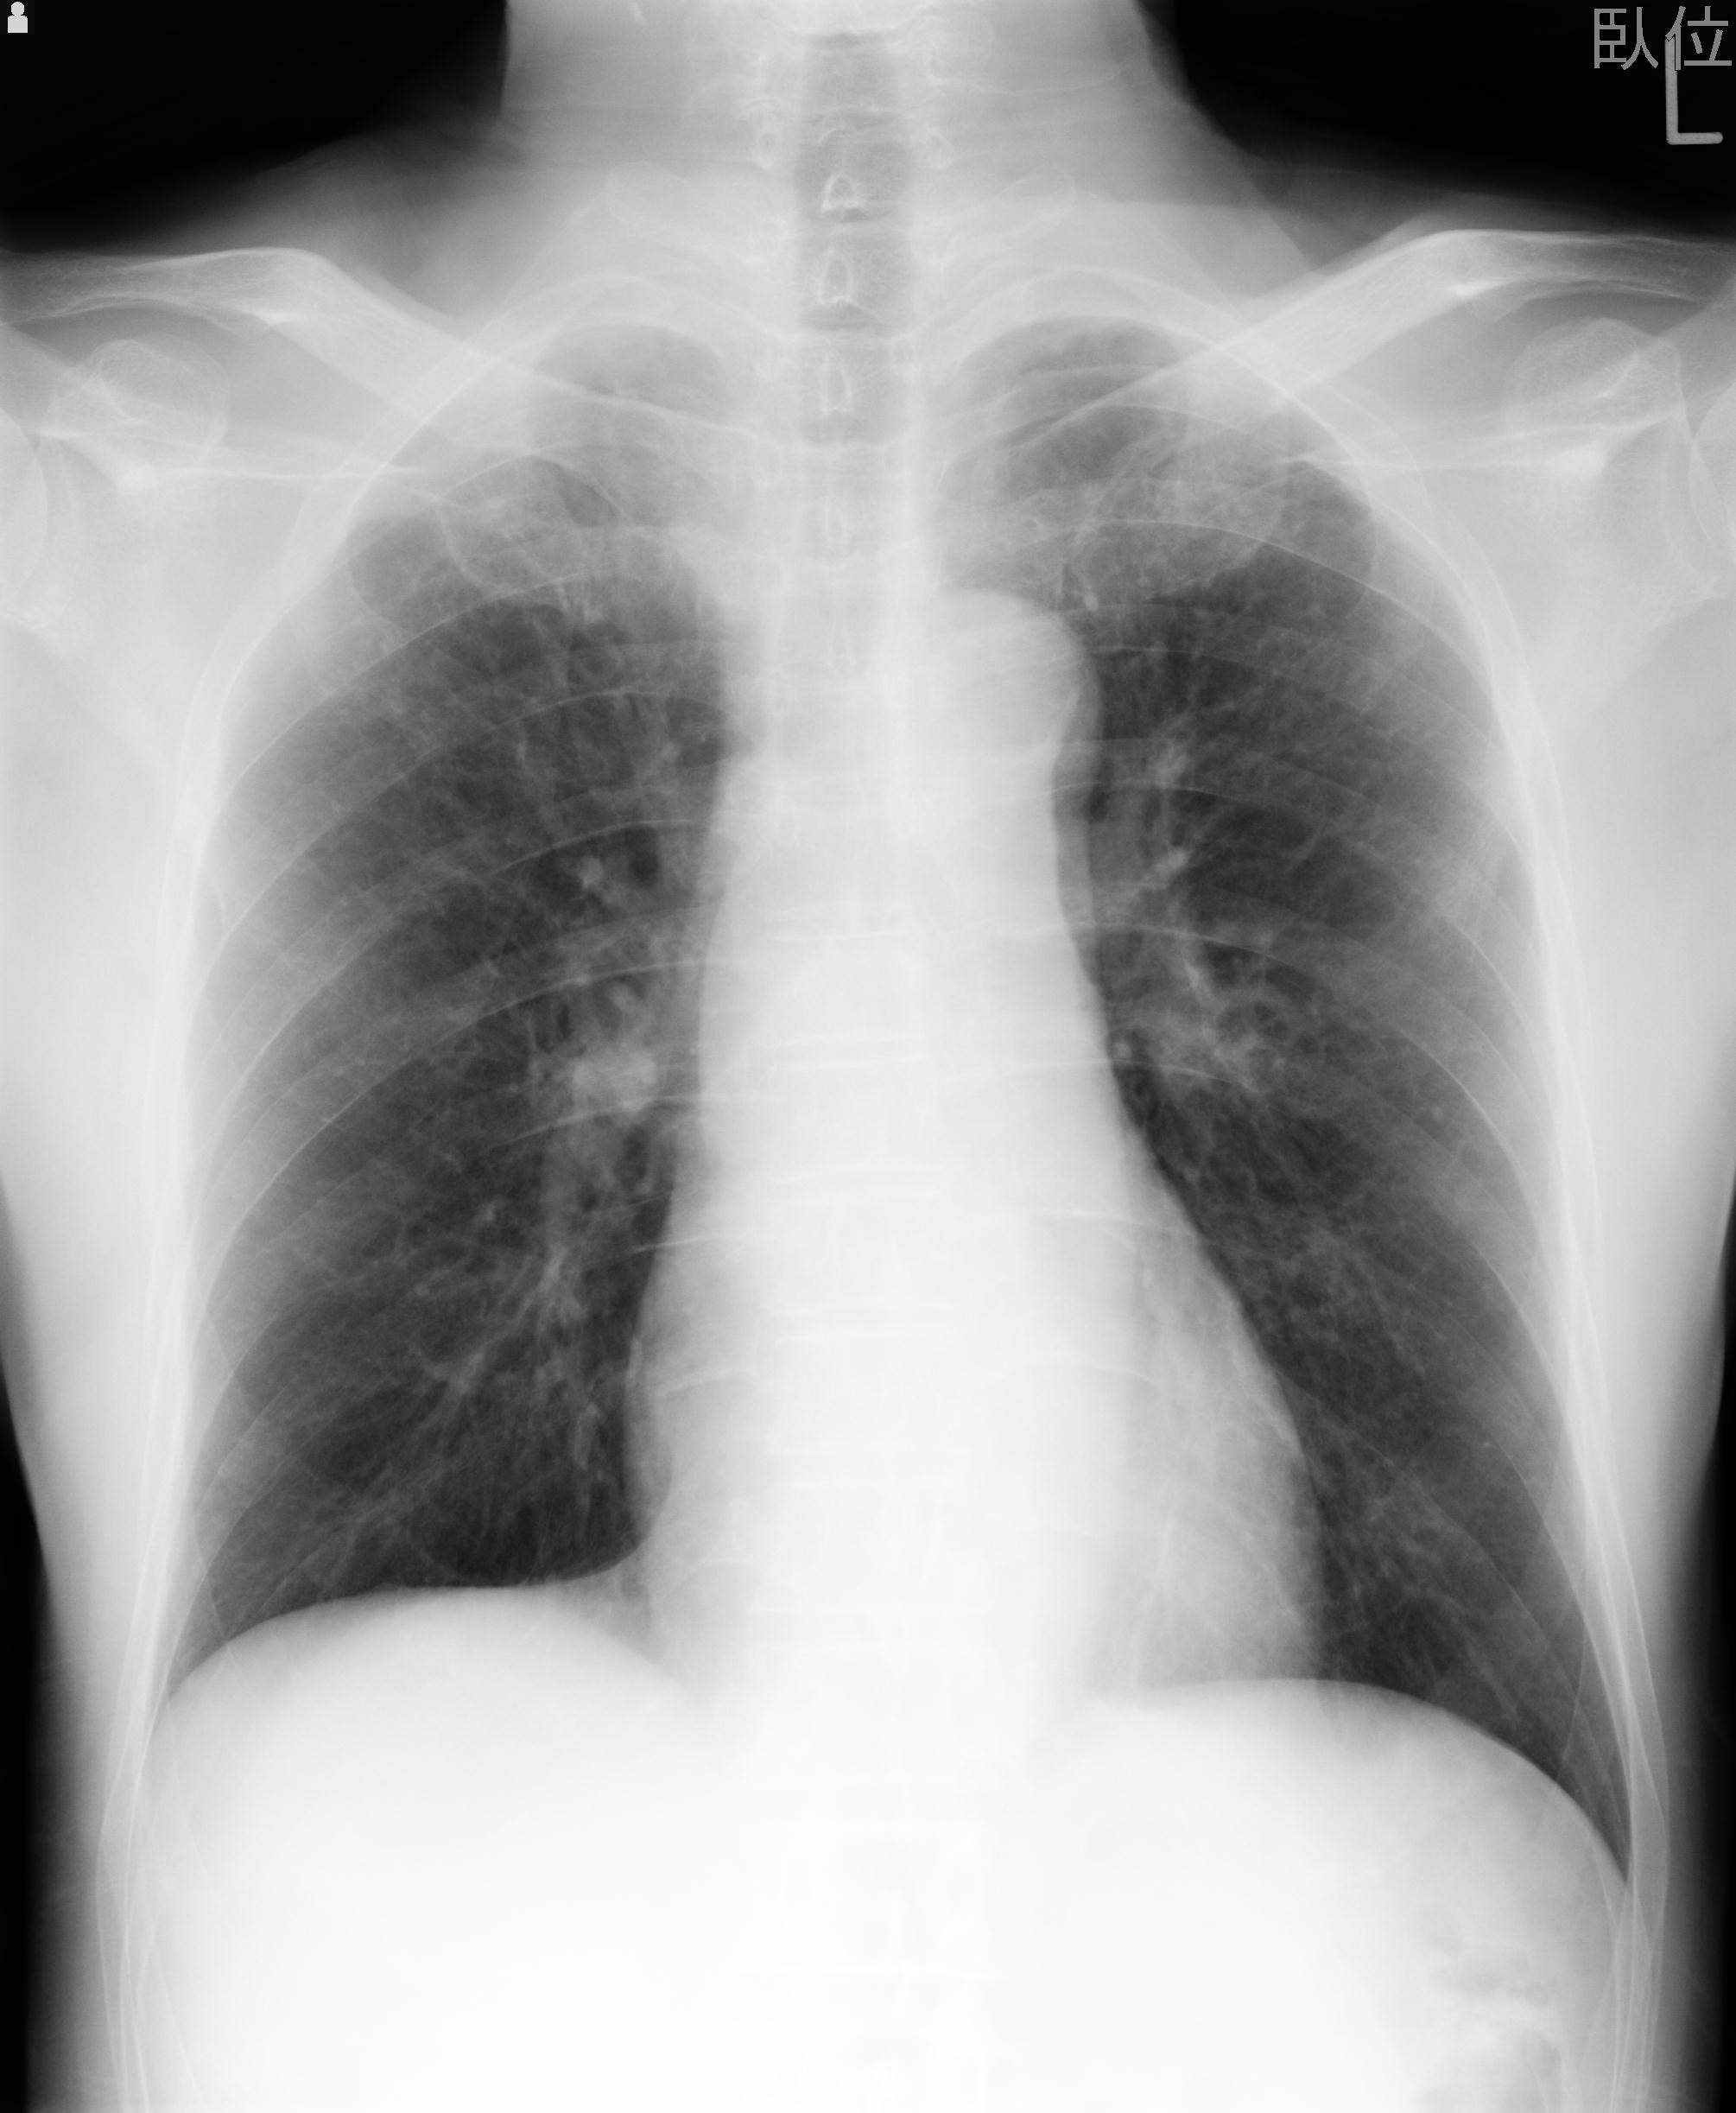

110214 12/20 肩 2R 12/21 肩 4R 72歳女性 左上腕外科頚プレート